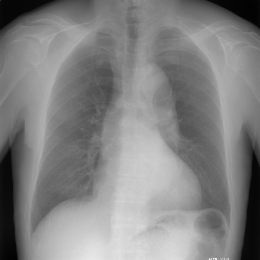

高精細表示サポート

医用画像表示専用の10ビットや12ビットグレースケール高精細液晶モニタを利用する場合に、表示装置の入力ビット数に合せた高ビット数の画像表示データを出力することが可能です。

また、特定メーカの表示装置を利用する場合は、表示API関数によって、自動的に高ビット数で画像データを表示することができます。

ImageClarityの高精細表示機能は、ImageClarityのほとんどの強力な表示機能をサポートしています。

高精細表示の原理

ImageClarityは、「高精細出力モード」を持っています。 この出力モードは、DICOM画像特有の階層情報をより忠実に表示できます。 通常出力モードの場合、8ビット以上の階層情報を持っている画像でも、一旦8ビットに変換してから出力しているのに対し、高精細出力モードの場合、高精細モニターがサポートできるビット数に併せて変換することにより、多くの階層情報を保つことが可能になります。